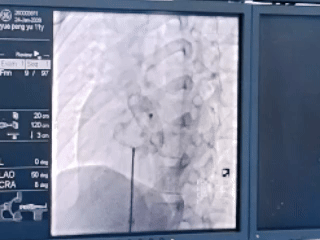

释放封堵装置,推拉稳固锚定点

而封堵治疗仅在腿部以2-4mm的穿刺伤口便可实施心内缺损的封堵,不损伤心内结构,术后2-3天即可出院,做到无痕愈合,是目前治疗继发孔型房间隔缺损首选的微创治疗方案。